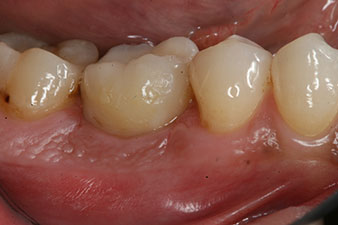

Damit konnten eine erfolgreiche Osseointegration und ausreichende biologische Stabilität dokumentiert werden, die eine Abformung in derselben Sitzung erlaubte.

Die Abschlussbilder zeigen die verschraubte monolithische Kompositkrone in situ und die Röntgenkontrolle (Abb. 9 und 10) (6).